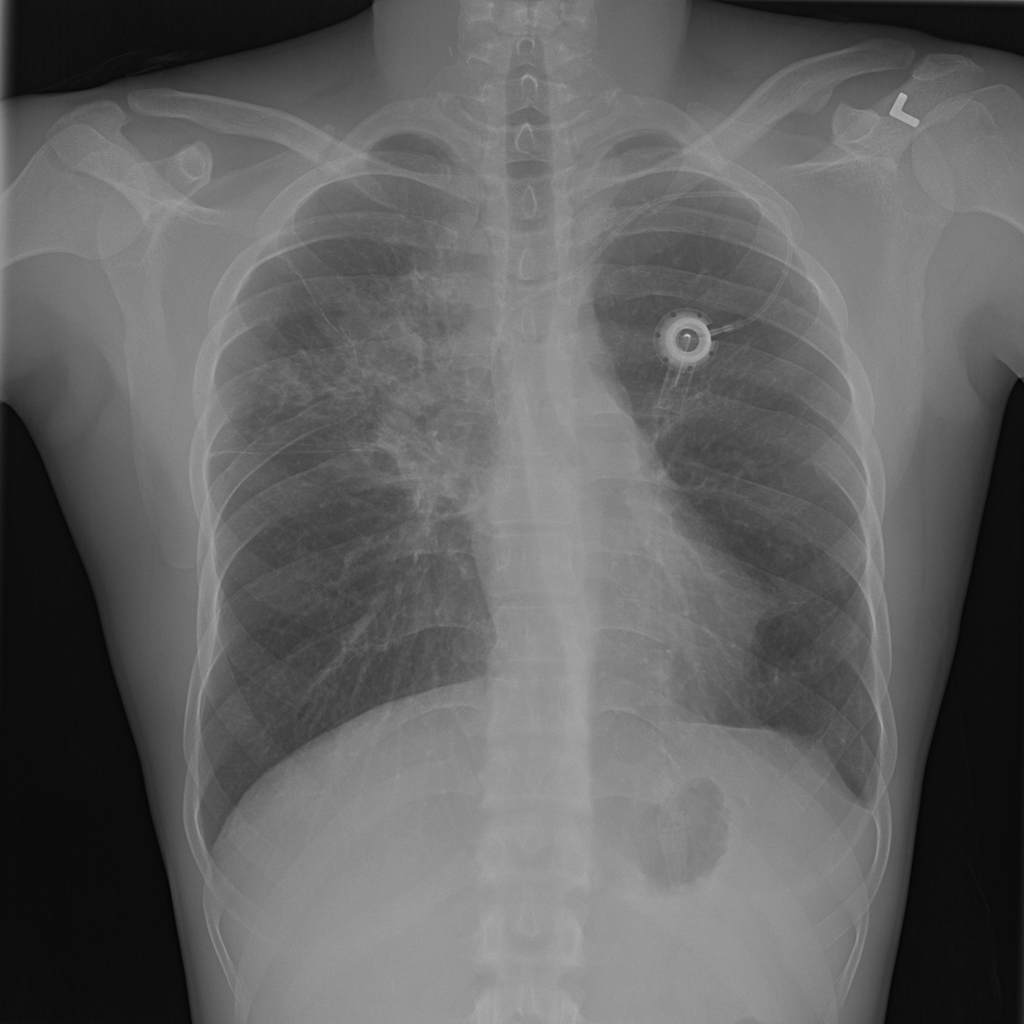

Showing up to 90 reference images for Pneumonia.

PAT-EBE1 · IMG-019Pneumonia

PAT-EBE1 · IMG-019

AP